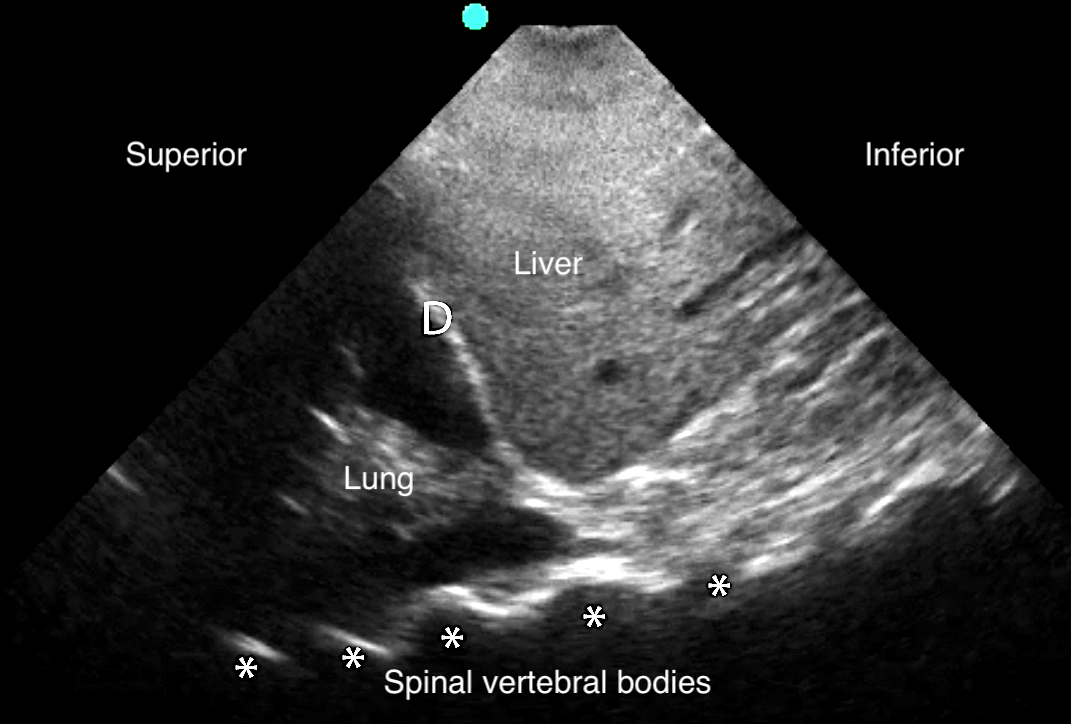

Pleural Effusion

- Anechoic space between parietal and visceral pleura78

- Normal air-filled lung is replaced by liquid-dense effusion, which now allows propagation of sound waves.

- Figure 18. Pleural effusion with spine sign